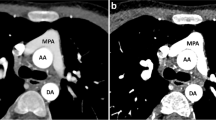

Patients with complex congenital heart disease (CHD) with single-ventricle physiology often undergo a series of staged palliative surgical procedures that typically end with a final-stage Fontan procedure which connects the systemic and pulmonary circulation in series via a Total Cavopulmonary Connection [1,2,3,4,5]. The intermediate-stage Glenn procedure re-routes blood typically from the superior vena cava (SVC) to the pulmonary arteries via an anastomosis of the SVC to the superior aspect of the right pulmonary artery (RPA). The Fontan procedure completes the separation of oxygenated from de-oxygenated blood by re-routing blood returning from the inferior vena cava (IVC) to the pulmonary arteries. Currently, the Fontan procedure typically involves either a lateral tunnel or an extracardiac Fontan completion with the latter being favored at our institution. The lateral tunnel Fontan incorporates the posterior wall of the right atrium with a patch to create a conduit from the IVC to the pulmonary arteries through the right atrium [2,3,4]. The extracardiac Fontan utilizes an extracardiac conduit to connect the IVC to the pulmonary arteries directly and bypasses the right atrium completely [5]. Despite advancements in surgical techniques, the anastomosis of the IVC to the pulmonary circulation in the extracardiac Fontan procedure is typically made to the under-surface of the RPA in a position that is slightly offset from the SVC anastomosis thus creating preferential blood flow from the SVC versus the IVC to the different branch pulmonary arteries [6, 7].

Various alterations to the traditional CTA PE protocol have been developed to overcome the differential streaming of contrast medium by focusing on the number of sites for contrast medium injection and the number of phases of acquisition [15, 16]. One technique utilizes dual sites of injection, one in an upper and one in a lower extremity vein, with a single acquisition. While another technique utilizes dual sites of injection and dual phases of acquisition. A third approach utilizes a single-site injection and single, late phase of acquisition. The fourth approach and one that is now favored by our team utilizes a single-site injection with dual phases of acquisition, also referred to as a biphasic CTA (Fig. 1). For biphasic CTAs, the initial acquisition typically evaluates the distal branch pulmonary arteries while the second acquisition evaluates the proximal Fontan circuit by allowing the contrast enough time for passive venous return. All four techniques have shown improvement over utilizing a single-site injection with single, early phase of acquisition. However, utilizing two IV sites to inject contrast is typically associated with double the discomfort with the added difficulty of obtaining venous access in a lower extremity that is of a sufficient caliber to allow for a power injection. Our study evaluated the use of a single-site injection with dual phases of acquisition compared to a single-site injection with a single, early phase of acquisition for optimal opacification of structures important for the evaluation of thromboembolic disease in the Fontan patient’s pulmonary circulation: SVC, IVC, Fontan, as well as the right and left branch pulmonary arteries.

In this study, we compared monophasic versus biphasic CTA protocols’ abilities to identify anatomical structures that are critical for evaluating thromboembolic disease in the Fontan circuit. Of the CTA scans using a biphasic protocol, 62.5% (10/16) were considered capable to clearly identify the critical structures of the Fontan circuit vs 27% (8/30) of the CTA scans using a monophasic protocol (p value = 0.027). Of the critical structures evaluated, using monophasic CTAs has given us the most difficulty evaluating the IVC, Fontan, and LPA (Table 4). With 70% of monophasic CTAs in our study utilizing a right upper extremity IV for contrast injection, these structures would be expected to be the least adequately filled as the typical streaming of contrast from the SVC is preferentially directed into the RPA due to the angle of anastomosis at the time of the Glenn procedure. Monophasic CTAs also led to three patients being inappropriately diagnosed with a thrombus in their Fontan circuit, two of which received inappropriate anticoagulation based on a flawed diagnosis. There were no biphasic CTAs that inappropriately diagnosed patients with a thrombus in their Fontan circuit.